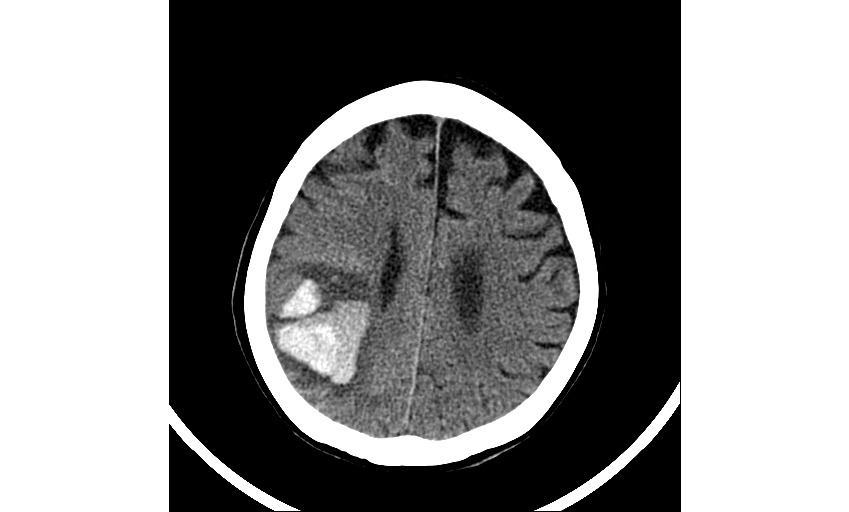

뇌내출혈은 뇌혈관이 파열되어 뇌조직 내에 출혈이 발생하는 심각한 질환으로, 신속한 치료가 이루어지지 않으면 생명에 위협을 줄 수 있습니다. 또한, 치료 후에도 다양한 후유증이 남을 수 있어 지속적인 관리와 재활이 필요합니다. 건강보험공단에서는 이러한 중증 뇌혈관질환 환자들을 위해 산정특례 제도를 통해 의료비 부담을 경감할 수 있는 혜택을 제공하고 있습니다. 이번 글에서는 뇌내출혈의 후유증, 수술적 치료 방법, 그리고 산정특례 제도의 적용에 대해 자세히 알아보겠습니다.

2. 뇌내출혈의 수술적 치료 방법

뇌내출혈의 치료는 출혈의 원인, 위치, 크기, 환자의 상태 등에 따라 결정됩니다. 수술적 치료는 다음과 같은 경우에 고려됩니다: